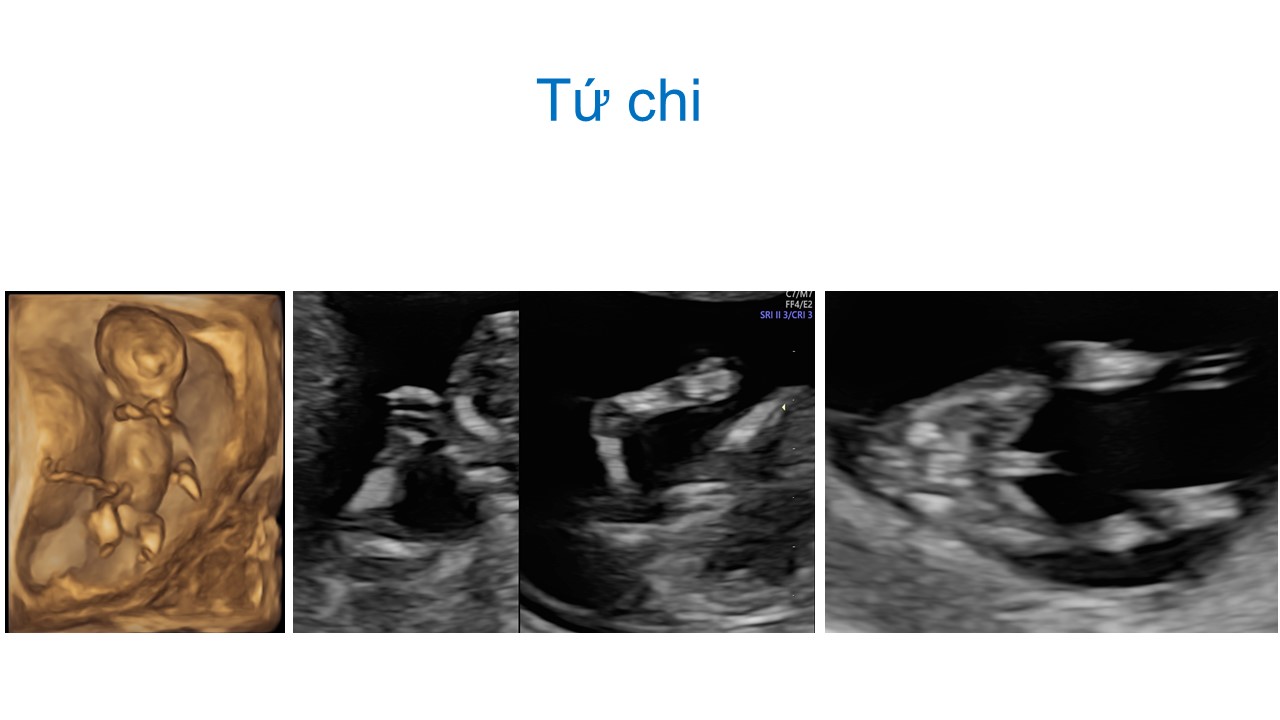

Siêu âm hình thai học quý I

ThS. BS CKII Nguyễn Đình Vũ - Khoa CĐHA, Bệnh viện Hùng Vương